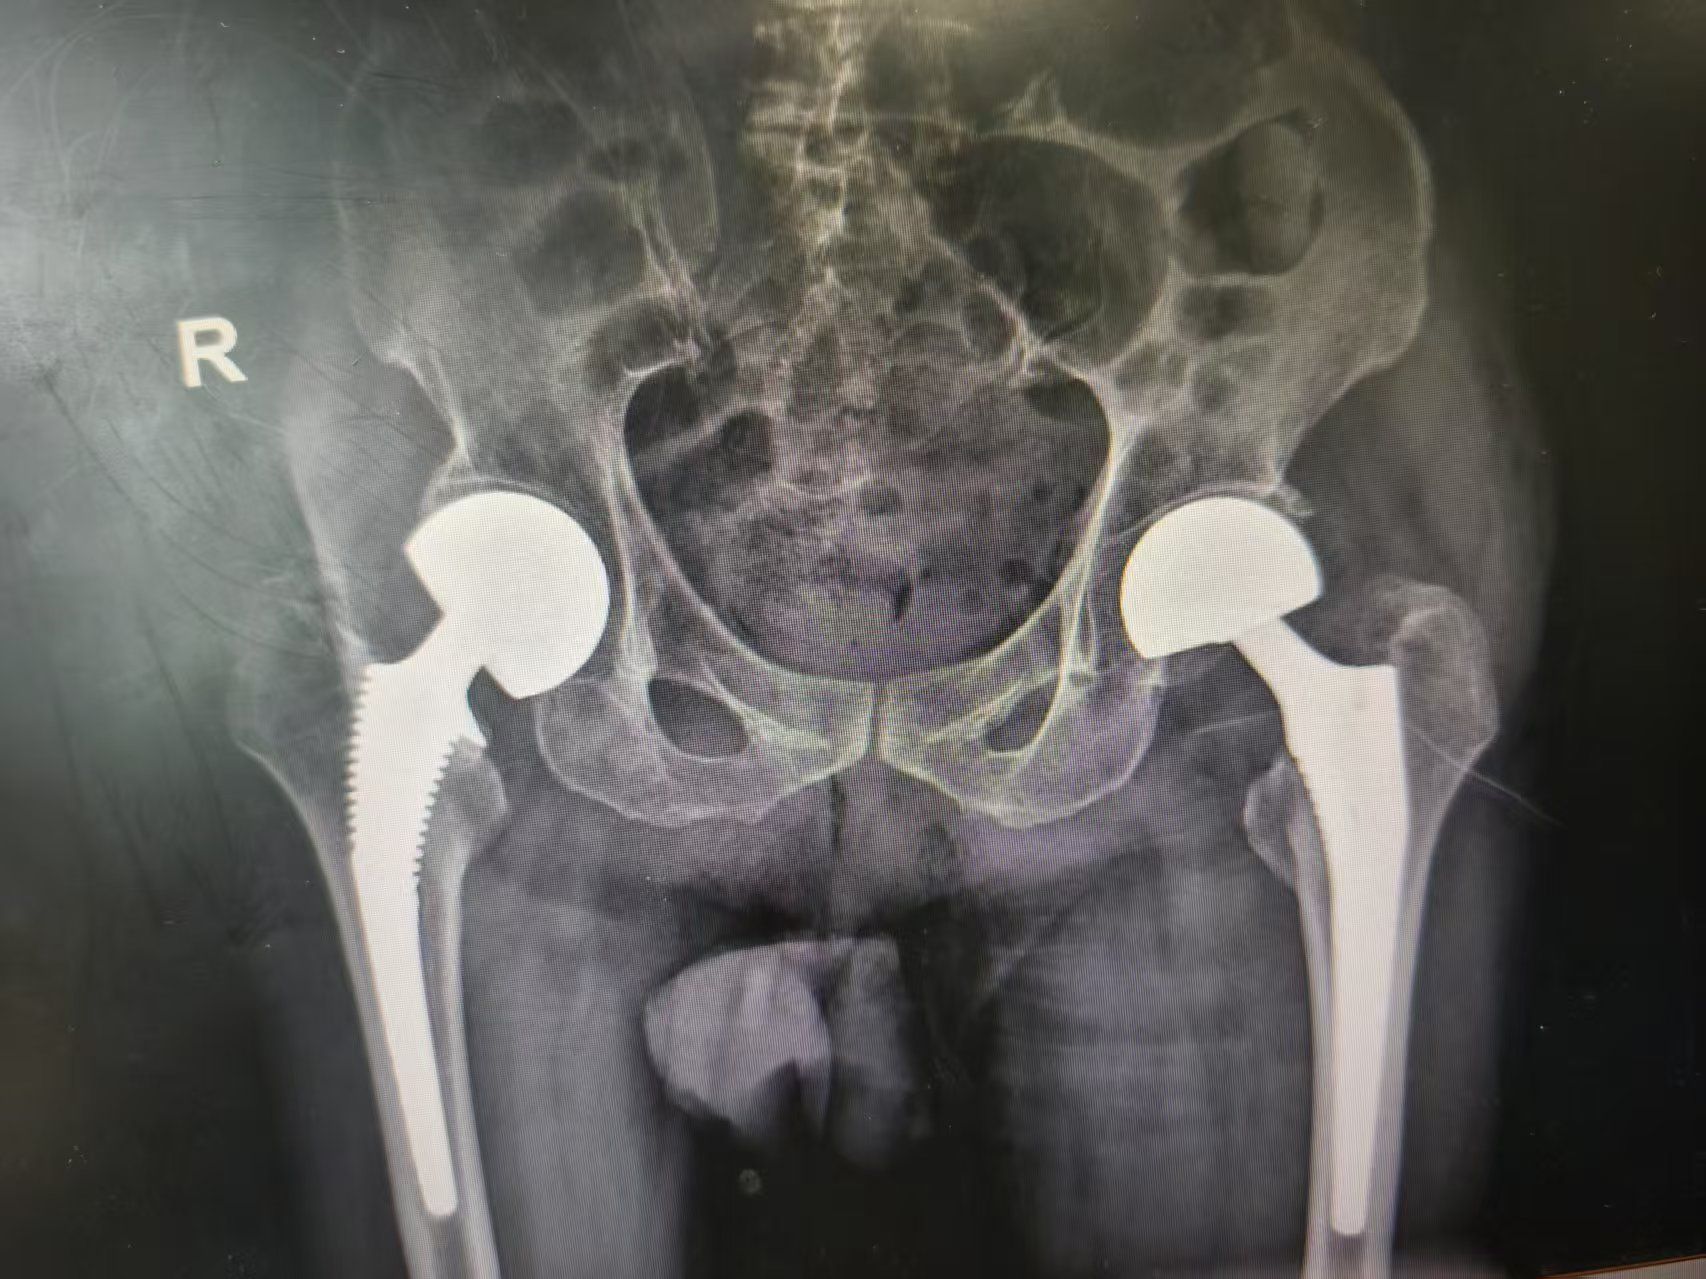

骨科主任医师鲁厚根与副主任医师陆圣君形成精密配合,在血管神经的间隙中穿行,拔除股骨头、清理髋臼窝内残留的圆韧带、植入生物型假体柄等操作一气呵成。“髋关节松紧合适,植入假体包容性好。”显示屏上银白色的假体与残存骨质完美嵌合,人工股骨头置换手术仅用时30分钟。

人工股骨头置换手术术后影像。